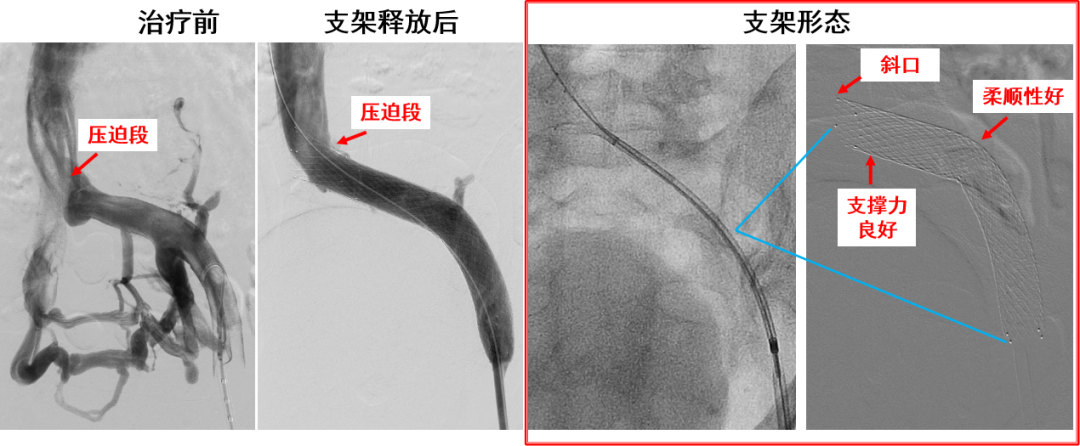

产品B:病例一

产品B:病例一(支撑力及分节衔接)

优点:

近心端斜口+喇叭口,防对侧血栓形成

近端长闭环设计,支撑力强

中间开环设计,柔顺性良好

延长段支架解决了单个支架长度不够覆盖病变段的问题

近端闭环部分可完全回收并重新释放定位

开环部分支撑力待加强